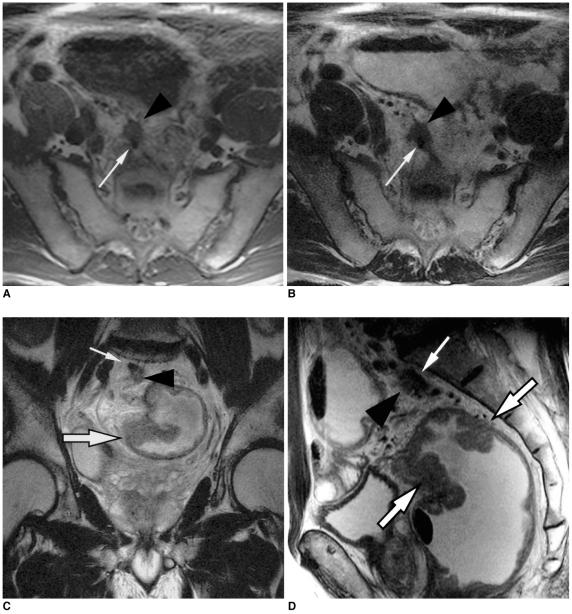

To determine the utility of MR imaging in evaluating the prognostic factors for a local recurrence of rectal cancer following a curative resection.

The preoperative MR images obtained from 17 patients with a local recurrence and 54 patients without a local recurrence, who had undergone a curative resection, were independently evaluated by three radiologists. The following findings were analyzed: the direct invasion of the perirectal fat by the primary rectal carcinoma, involvement of the perirectal lymph nodes, perirectal spiculate nodules, perivascular encasement, and an enlargement of the pelvic wall lymph nodes. The clinical and surgical profiles were obtained from the patients' medical records. The association of a local recurrence with the MR findings and the clinicosurgical variables was statistically evaluated.

RESULTS

Of the MR findings, the presence of perivascular encasement (p = 0.001) and perirectal spiculate nodules (p = 0.001) were found to be significant prognostic factors for a local recurrence. Of the clinicosurgical profiles, the presence of a microscopic vascular invasion (p = 0.005) and the involvement of the regional lymph nodes (p = 0.006) were associated with a local recurrence. Logistic regression analysis showed that the presence of perirectal spiculate nodules was an independent predictor of a local recurrence (odds ratio, 7.382; 95% confidence interval, 1.438, 37.889; p = 0.017).

The presence of perirectal spiculate nodules and perivascular encasement on the preoperative MR images are significant predictors of a local recurrence after curative surgery for a rectal carcinoma. This suggests that preoperative MR imaging can provide useful information to help in the planning of preoperative adjuvant therapy.